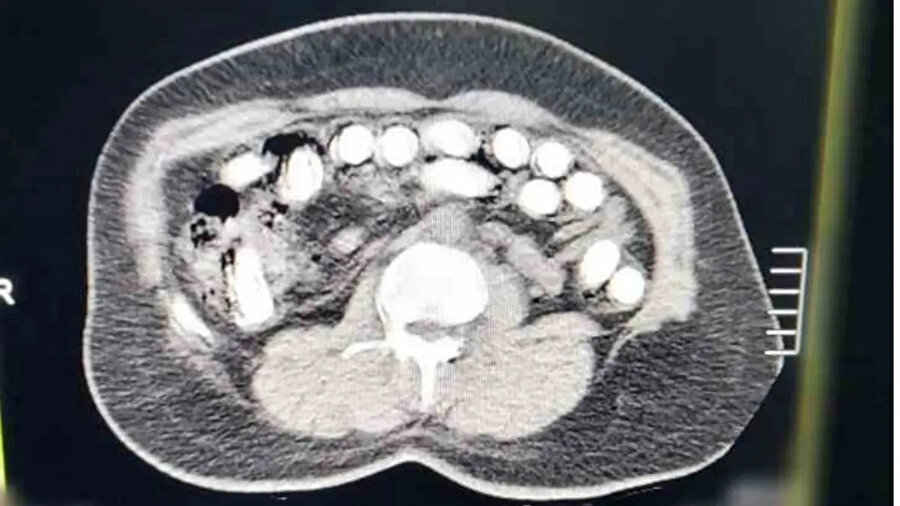

Bu kapsamda düzenlenen operasyonda A.R. (27) gözaltına alındı. Hastaneye sevk edilen kadın şüphelinin röntgen ve tomografi görüntülerinde, midesinde çok sayıda yabancı cisim bulunduğu tespit edildi.

50 kapsül içerisine gizlenmiş 500 gram uyuşturucu, yapılan tıbbi müdahaleyle çıkarıldı.